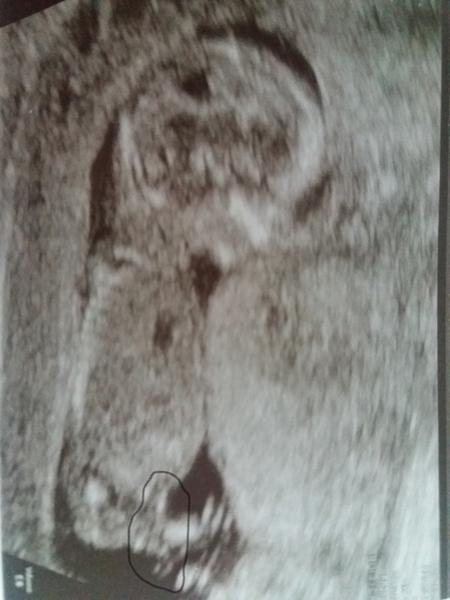

Přikládám foto ultrazvuku holčičky v 16tt pro ostatní maminky pro porovnani, je to zaber zespodu jakoby na prdku s roztazenyma nozkama 😉.

@mikejla_a ta tenká čárka v pravo dole by měl být pohl. hrbolek co směřuje nahoru 🙂

@mrnousek121 no me prave prijde,ze jde celkem rovnobezne s pateri...tak uvidime 😊

@fiendish.angel pokud je to za nožičkou pohlaví hrbolek tak by to měla týt holčička

@kristyna14092013 holčička. pohlavní hrbolek je souběžně s osou páteře. kdydy výrazně čněl nahoru, je to kluk 🙂